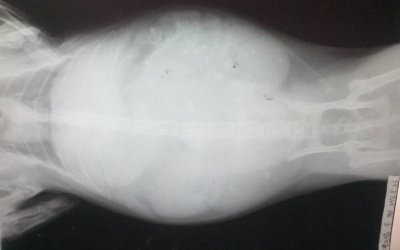

버림받은 X남이의 뱃속에서는 새생명이 자라고 있었으니..

아빠에게 버림받은 다섯 애기들의 운명은 어찌 될 것인가...

외롭게 혼자서 다섯 꼬물이를 출산합니다..